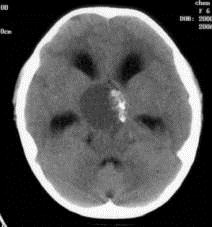

问题 病历摘要:??患者女性,6岁,半年来感觉视力模糊,近10天出现反复头痛,间有恶心呕吐,精神转差,查体:神志清楚,身高90cm,体重25Kg,血压90/55mmHg,右眼视力4.6,左眼视力4.8,双侧视乳头水肿,颈软,伸舌居中,四肢肌张力正常,肌力5级,双侧Babinski征(-)。 手术利用右侧翼点入路,在显微镜下利用鞍区自然间隙进行,一般来说,第二间隙可以窥见的结构有?

选项 A.右侧视神经 B.右侧大脑前动脉 C.前交通动脉 D.垂体上动脉 E.Heubner?回返动脉 F.颈内动脉床突上段 G.基底动脉 H.右侧小脑前下动脉

答案 ADFG

解析 ADFG